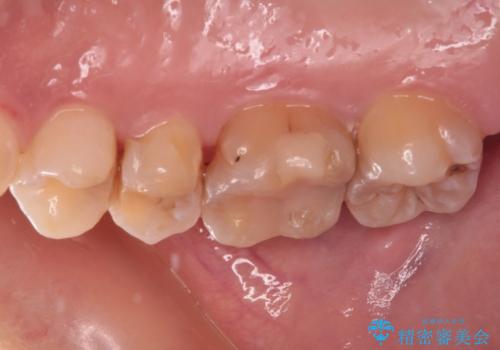

- 以前詰め物をした奥歯に物が頻繁に挟まるとのことで来院された患者様です。

充填物は形態が不正であり、歯肉付近にバリのように充填材料が飛び出していたため、歯肉が腫れやすい状態でした。

精密に治療を行うため、型取りを行った上でセラミックインレーによる修復治療を行うこととしました。